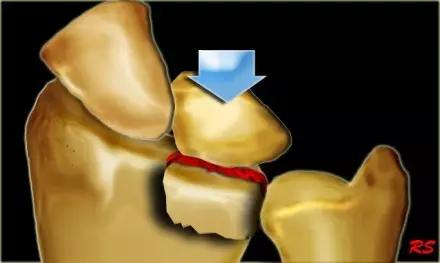

全肱骨小头骨折,为一种少见的关节内骨折,多见于成年人。常由于跌倒时手过度伸直或在屈肘时因桡骨小头撞击肱骨小头,并同时有外翻力存在时发病,亦可伴有滑车骨折与内侧副韧带的撕裂。X 线表现为全肱骨头骨折,向上移位。

Hahn-steinthal 骨折 X 片(来源:Hahn-Steinthal fracture: a case report.BioMed central Cases Journal20081:239)

Hahn-steinthal 骨折 CT 片(来源:Hahn-Steinthal fracture: a case report.BioMed central Cases Journal20081:239)